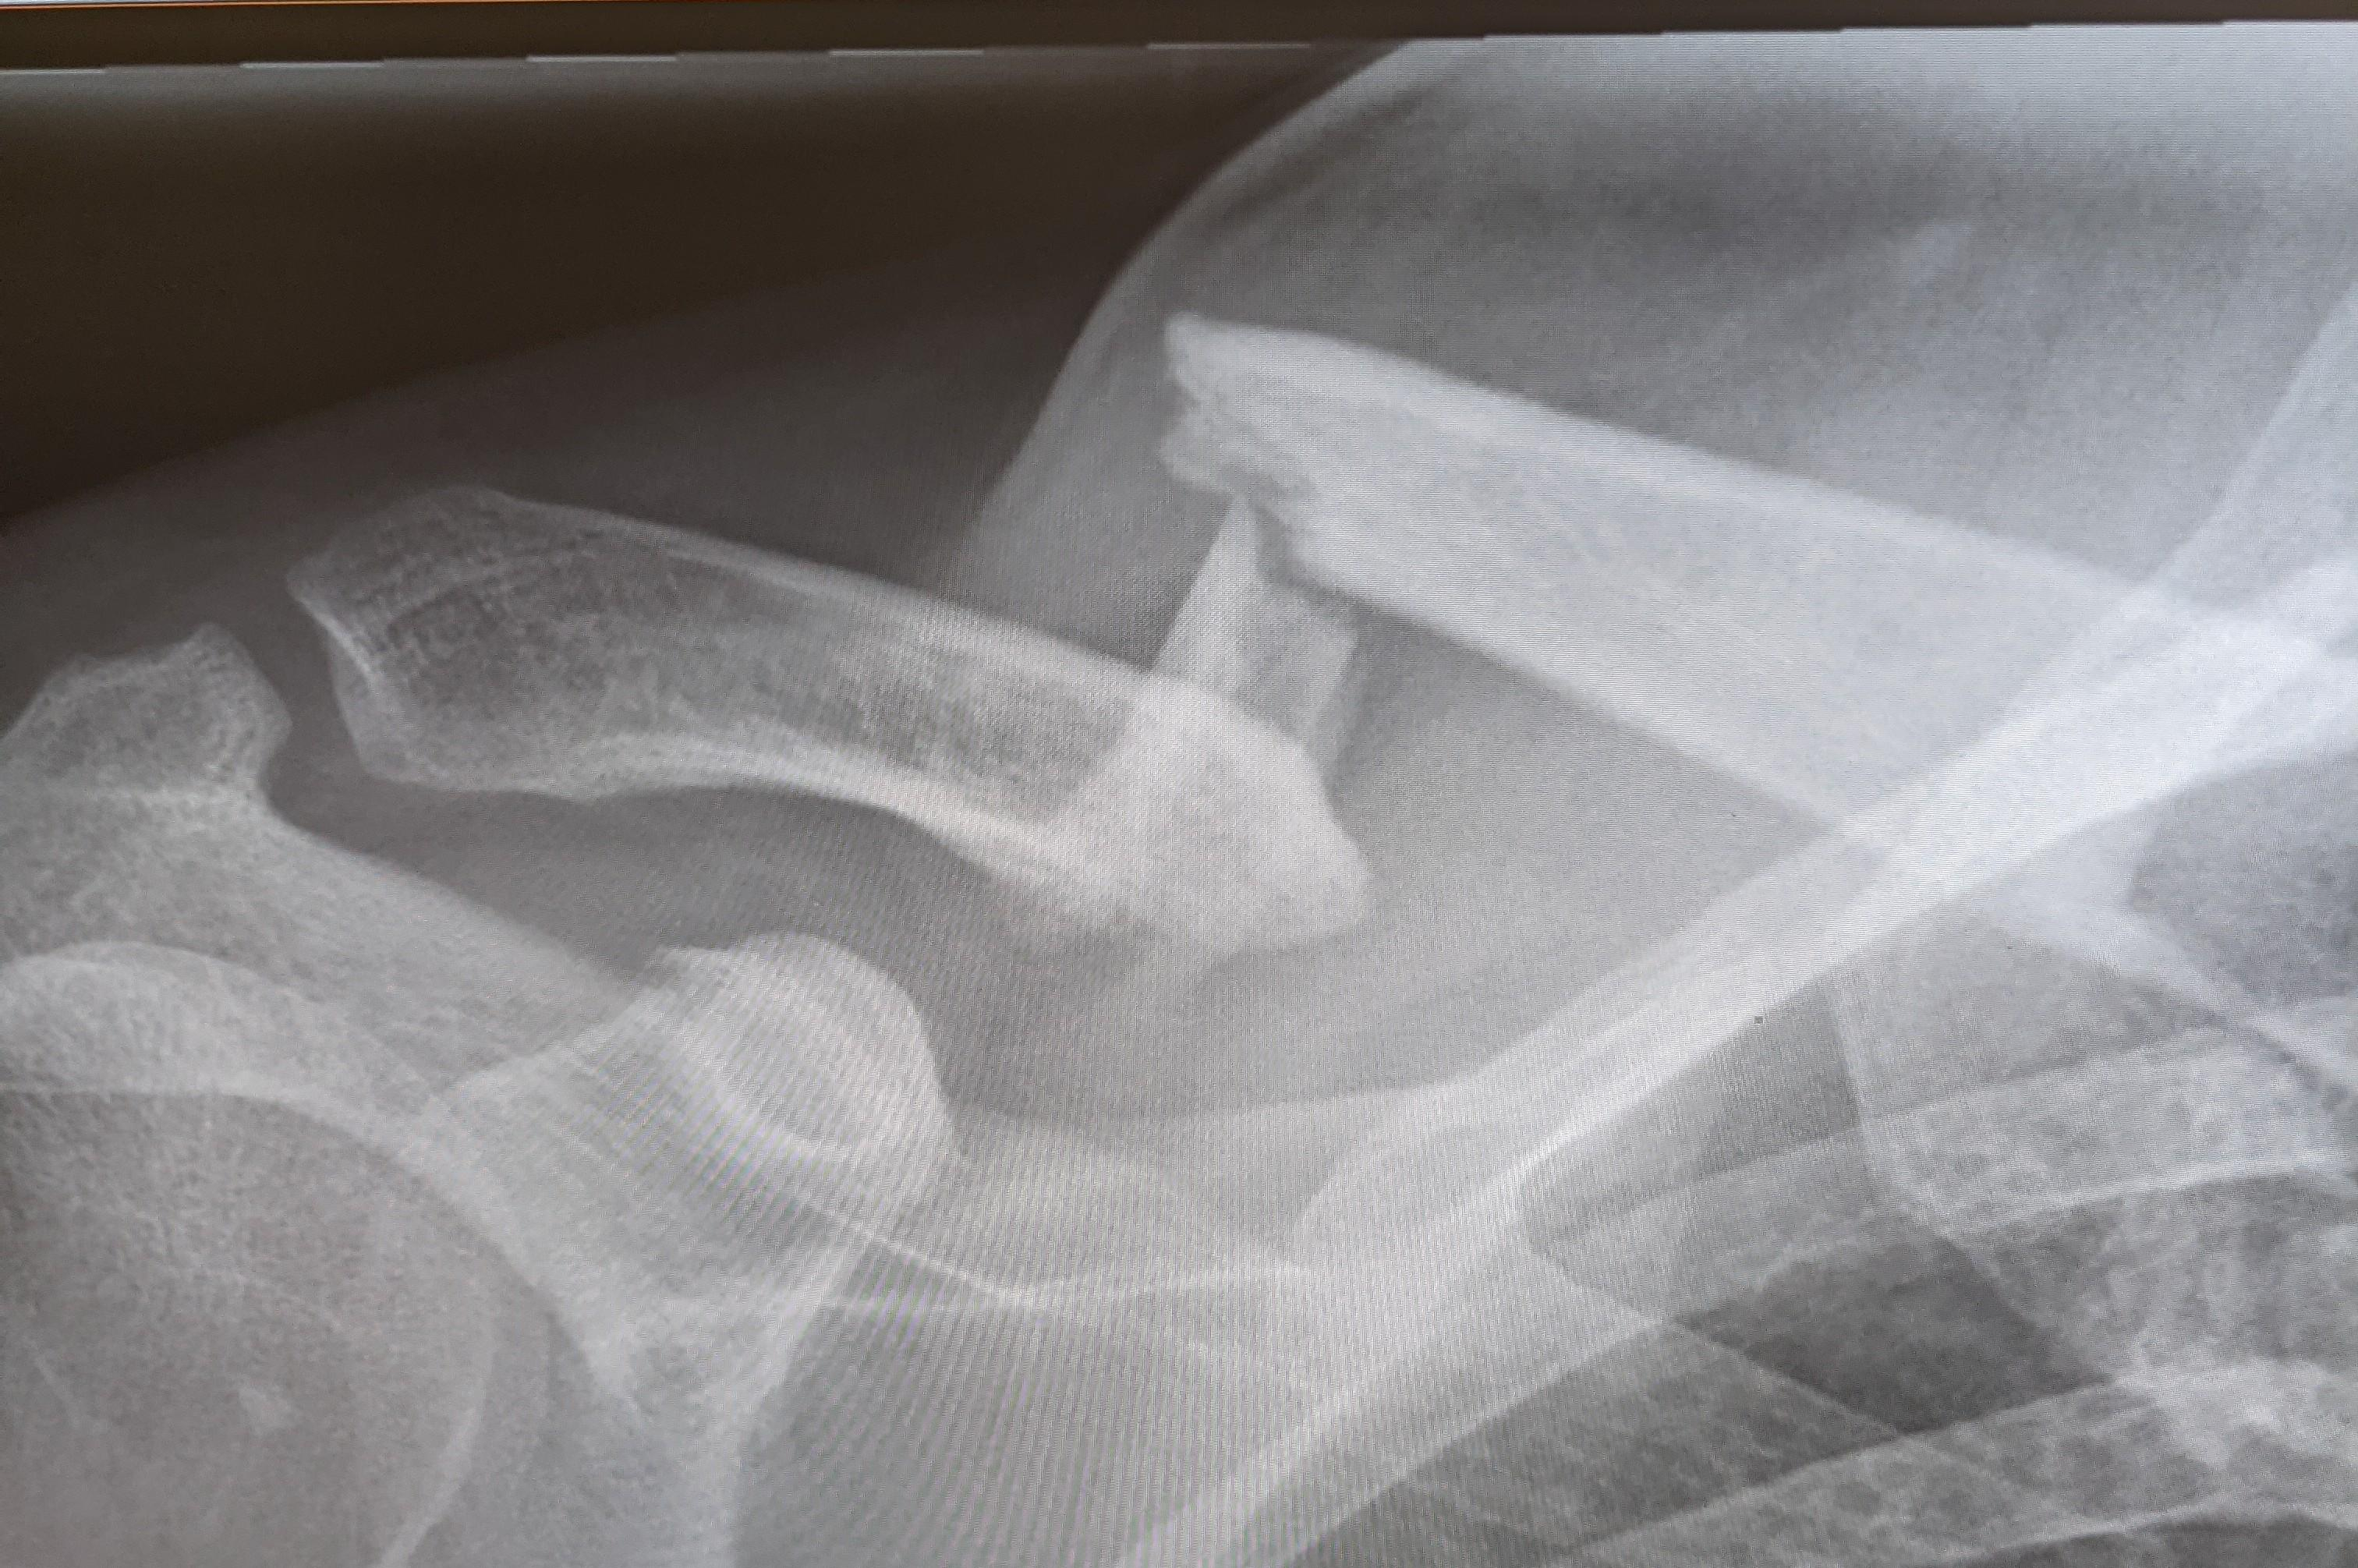

Forsøk på bilde. Crop,a for å få ned str.

Burde vise tydelig Z. Den ble kanskje mer enn klump når det er grodd.

Det jeg ikke visste som var nytt for meg denne gangen er bekymring for lungene, punktering når bruddet blir sånn. Lungene går visst høyt opp i skulder! De har sjekket meg grundig for pust og får jeg antydninger til dårlig pust er det 113!

Vedlegg

PXL_20210710_011304637~2.jpg (2.66 MB, 201 nedlastinger)

Har ingen kvalifikasjoner overhodet for å vurdere røntgenbildet, men for mitt komplett utrente øye, ser bruddet grovt ut. Håper du får grundig råd, slik at du får grunnlag for å ta en avgjørelse.